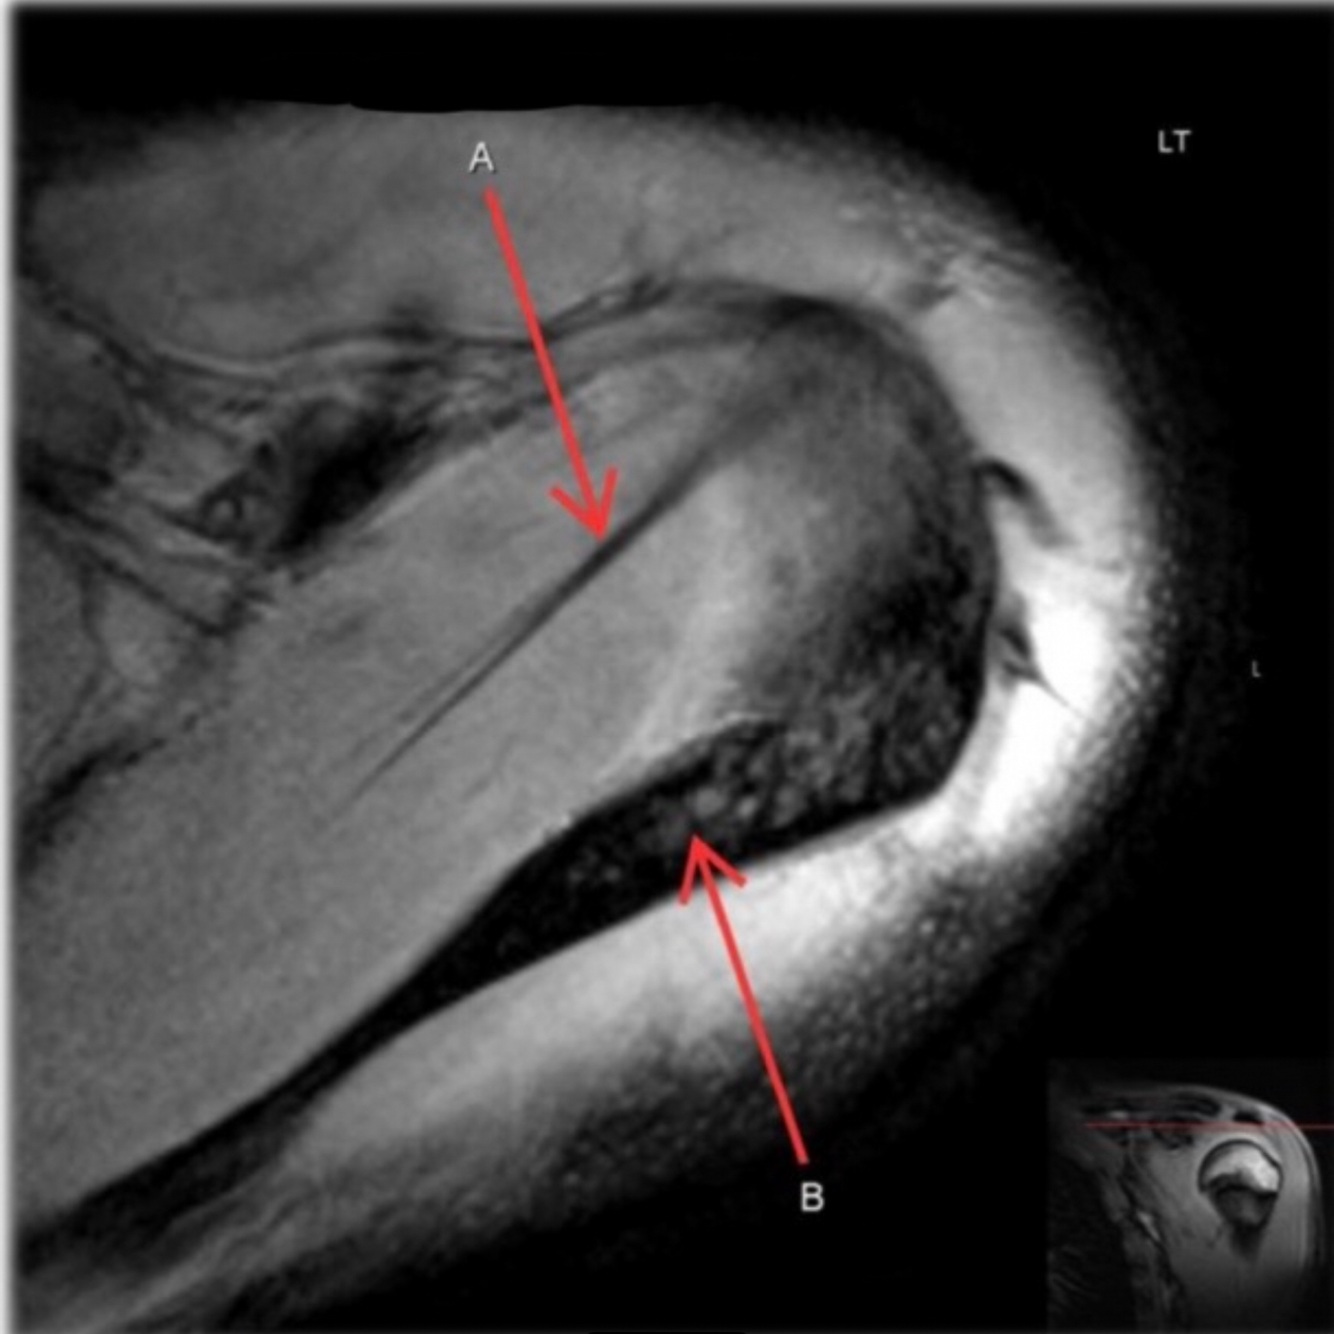

How well did you know this?

1

Not at all

2